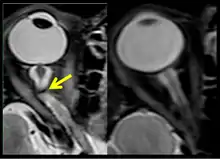

The third case of visual changes while on board the ISS had no changes in visual acuity and no complaints of headaches, transient visual obscurations, diplopia or pulsatile tinnitus during the mission. Upon return to Earth, no eye issues were reported by the astronaut at landing. Fundus examination revealed bilateral, asymmetrical disc edema. There was no evidence of choroidal folds or cotton-wool spots, but a small hemorrhage was observed below the optic dics in the right eye. This astronaut had the most pronounced optic-disc edema of all astronauts reported to date, but had no choroidal folds, globe flattening or hyperopic shift. At 10 days post landing, an MRI of the brain and eyes was normal, but there appeared to be a mild increase in CSF signal around the right optic nerve.[5]

The sixth case of visual changes of an ISS astronaut was reported after return to Earth from a 6-month mission. When he noticed that his far vision was clearer through his reading glasses. A fundus examination performed 3 weeks postflight documented a grade 1 nasal optic-disc edema in the right eye only. There was no evidence of disc edema in the left eye or choroidal folds in either eye (Figure 13). MRI of the brain and eyes days postflight revealed bilateral flattening of the posterior globe, right greater than left, and a mildly distended right optic nerve sheath. There was also evidence of optic-disc edema in the right eye. A fundus examination postflight revealed a "new onset" cotton-wool spot in the left eye. This was not observed in the fundus photographs taken 3 weeks postflight.[5]

The seventh case of visual changes associated with spaceflight is significant in that it was eventually treated postflight. Approximately 2 months into the ISS mission, the astronaut reported a progressive decrease in his near and far acuity in both eyes. The ISS cabin pressure, CO2 and O2 levels were reported to be within normal operating limits and the astronaut was not exposed to any toxic substances. He never experienced losses in subjective best-corrected acuity, color vision or stereopsis. A fundus examination revealed a grade 1 bilateral optic-disc edema and choroidal folds (Figure 15).[5]